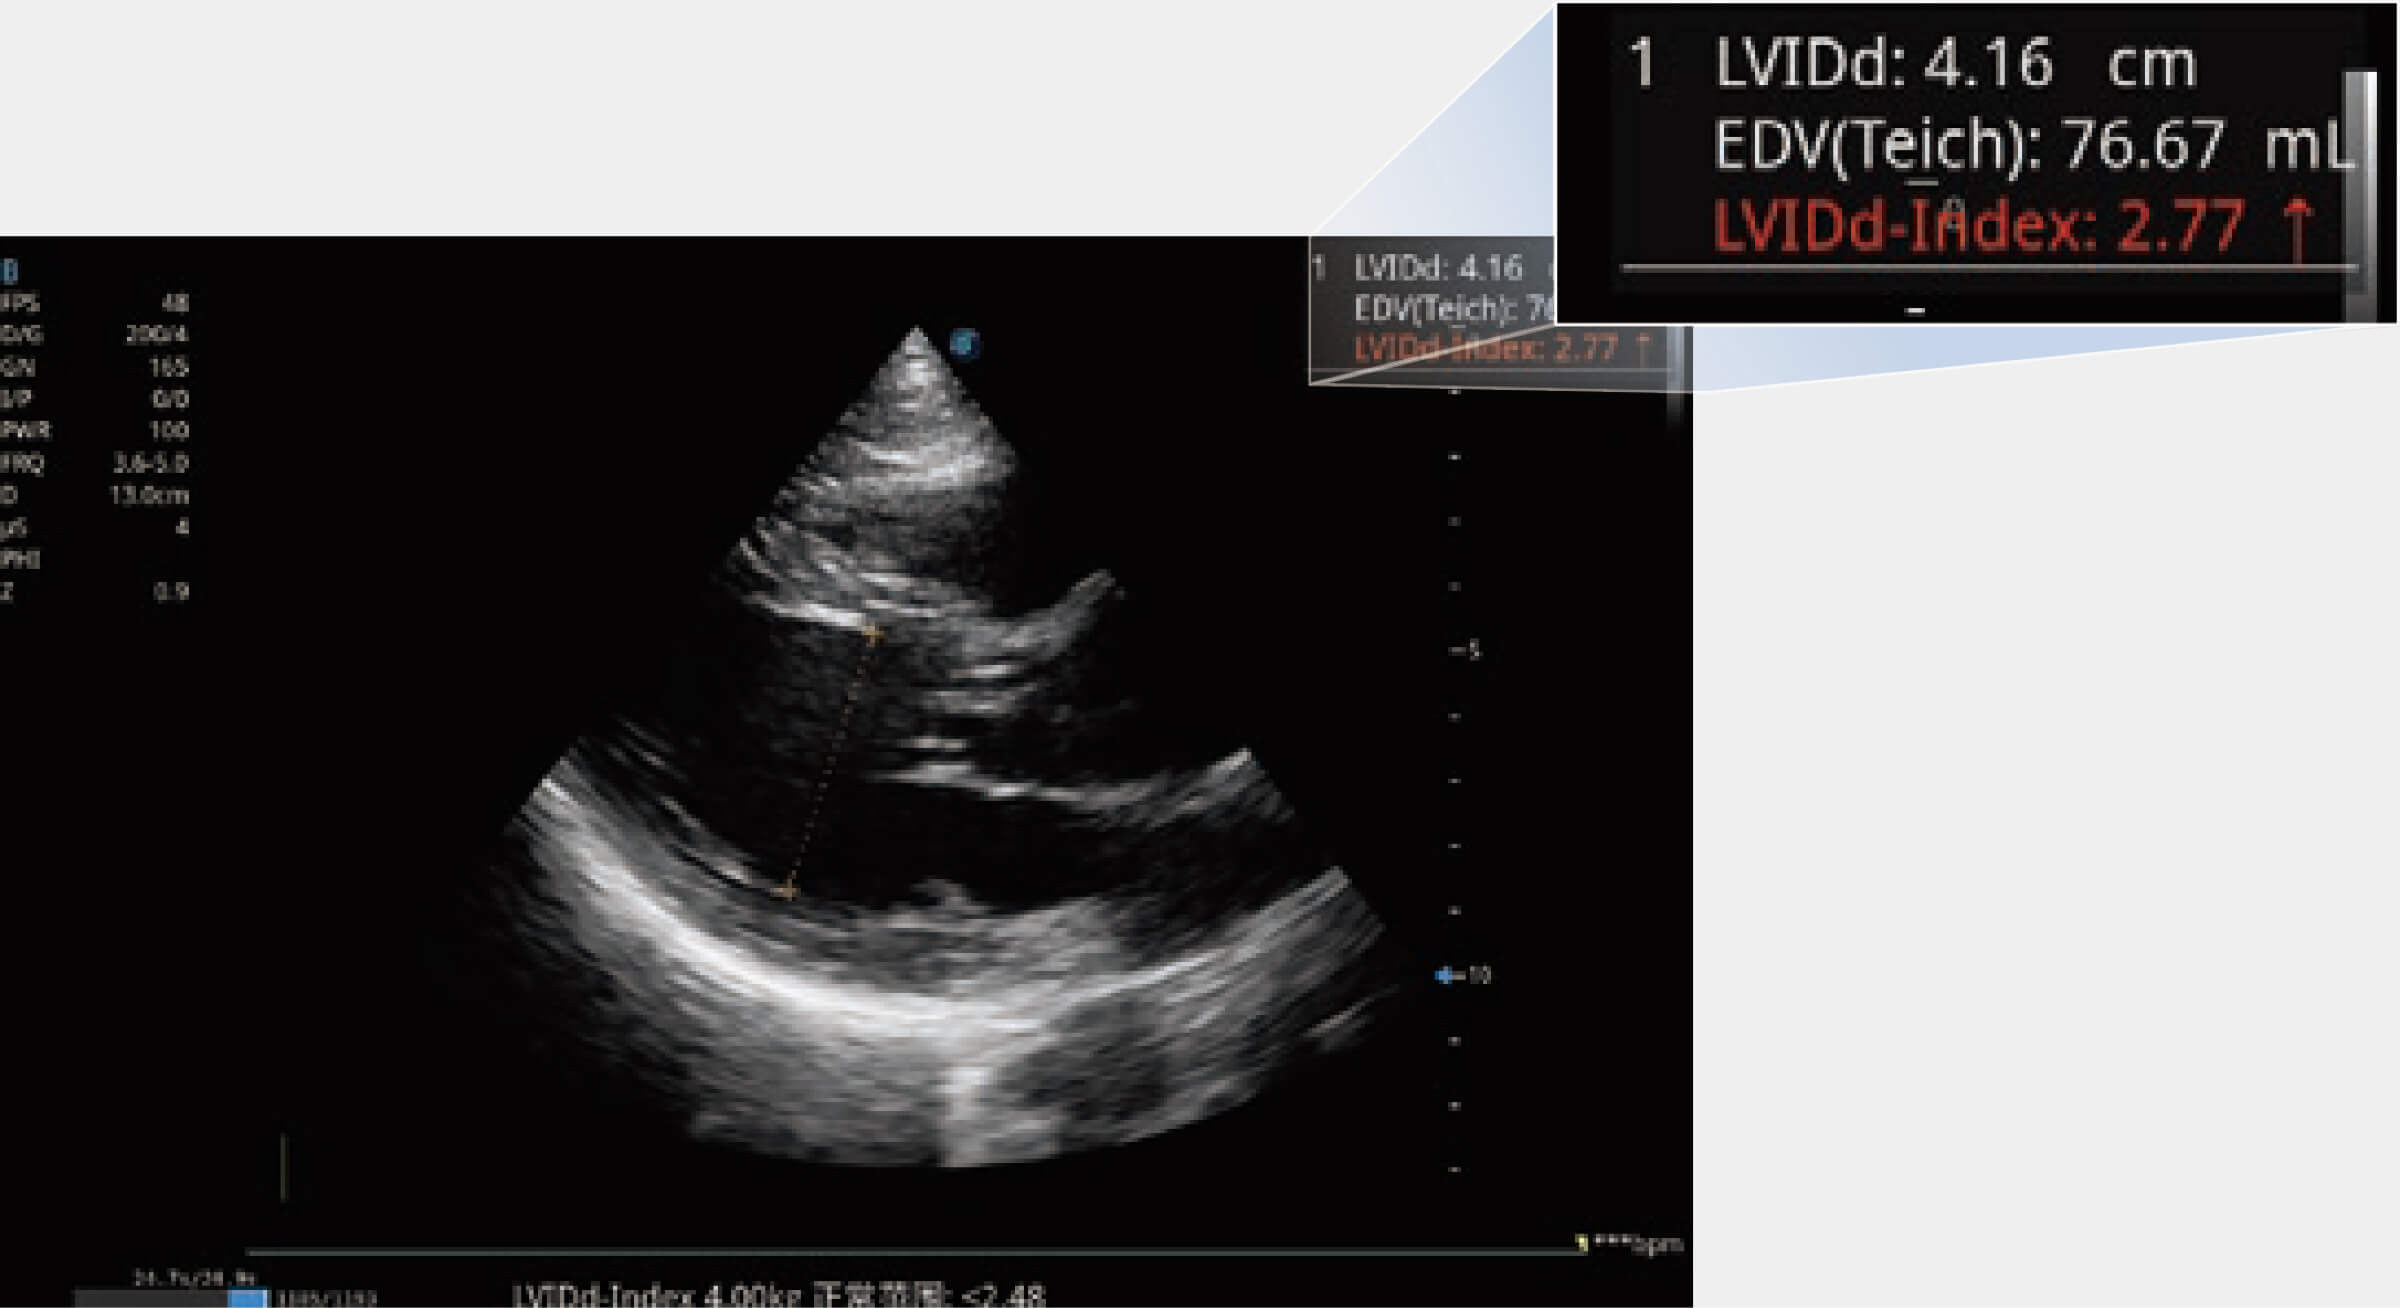

当心脏测量结果超出正常范围时,可实时预警提示动物医生,减少疾病漏诊概率。